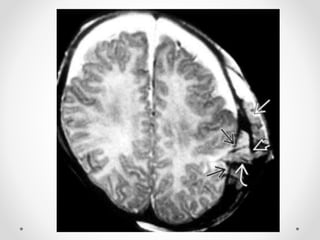

1. Thoát vị dưới liềm đại não (TV hồi đai)

CĐHA:

- Hình ảnh trực tiếp: hồi đai và thể trai thoát vị sang bên

đối diện

- Hình ảnh gián tiếp:

- Giãn não thất bên bên đối diện do chèn ép lỗ monro

- Di lệch các cấu trúc đường giữa.

- Trường hợp nặng, chèn ép ĐM quanh chai, ĐM viền

chai gây nhồi máu hồi đai, thể chai, nhu mô não thuỳ

trán